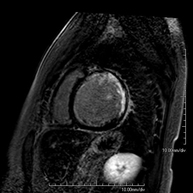

This non-invasive diagnostic test yields morphological and functional information about the heart and adjacent structures. In this way, different congenital and acquired pathologies can be diagnosed, or checks can be carried out on patients with previously known pathologies. In the vast majority of cases, intravenous contrast (gadolinium) is required to complete the study. This type of contrast rarely causes adverse reactions. During the test, the technician will ask the patient to hold their breath several times for 10–15 seconds to obtain the clearest images possible. No prior preparation is required by the patient. The test lasts approximately 45–60 minutes. It is not recommended for patients with pacemakers. Patients should nevertheless inform the doctor if they have metal implants and/or surgical clips.